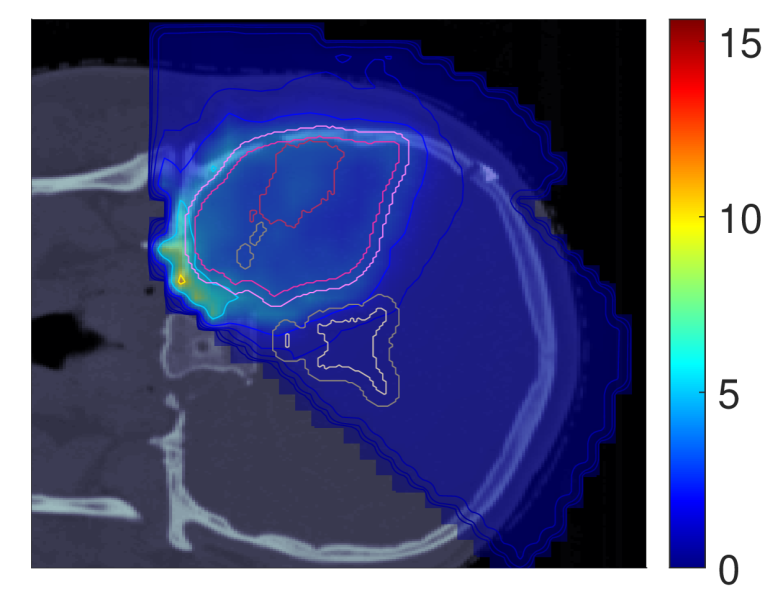

In light of the dose distribution changes and the interdependency between dose and dose-averaged LET, we can identify patterns in the slice images with the optimal dose-averaged LET distributions shown in Figure 5.

NTCP30 %NTCP\approx{$30\text{\,}\mathrm{\char 37\relax}$} NTCP20 %NTCP\approx{$20\text{\,}\mathrm{\char 37\relax}$} NTCP10 %NTCP\approx{$10\text{\,}\mathrm{\char 37\relax}$}

ldl_{d} (NTCPp)(NTCP_{p})

Refer to caption Refer to caption Refer to caption

ldl_{d} (LSEp~)(LSE_{\tilde{p}})

ldl_{d} (H~p)(\tilde{H}_{p})

ldl_{d} (H~p~)(\tilde{H}_{\tilde{p}})

Figure 5: Optimal slice images of the dose-averaged linear energy transfer ldl_{d} (in keV/μ\boldsymbol{\mu}m) for NTCPpNTCP_{p}, LSEp~LSE_{\tilde{p}}, H~p\tilde{H}_{p} and H~p~\tilde{H}_{\tilde{p}} at different NTCP levels. The shifts in ldl_{d} coincide with those observed on the slice images for dRBE,fxd_{RBE,fx}, i.e., there seems to be a trade-off between dRBE,fxd_{RBE,fx} and ldl_{d} that is consistent with the mathematical structure of the POLO model. As a result, the ldl_{d} slice images for NTCPpNTCP_{p} and H~p\tilde{H}_{p} are almost equivalent, while LSEp~LSE_{\tilde{p}} and H~p~\tilde{H}_{\tilde{p}} differ. For the latter two objective functions, the shift of dRBE,fxd_{RBE,fx} outside the target volume appears to be crucial, or, respectively, no shift of ldl_{d} is necessary due to the strength of the reduction of dRBE,fxd_{RBE,fx}.

First, we note that ldl_{d} hotspots do not manifest in the high dose regions – this would be a risk driver because of the product term in the POLO model from Section II.A. Generally, some trade-off between dRBE,fxd_{RBE,fx} and ldl_{d} is evident, where the optimizer allows for higher values of ldl_{d} when dRBE,fxd_{RBE,fx} has been sufficiently reduced, and vice versa.

For NTCPpNTCP_{p}, the slight reduction of dRBE,fxd_{RBE,fx} outside the target volume coincides with a redistribution of ldl_{d}: higher values in the target volume are prevented, and instead induced along the margins of the PTV. Once again, H~p\tilde{H}_{p} behaves almost identically. Following the dose/LET trade-off, the almost unchanged values for LSEp~LSE_{\tilde{p}} can also be explained: LSEp~LSE_{\tilde{p}} minimally reduces dRBE,fxd_{RBE,fx} in the region of overlap with the VS, meaning that high ldl_{d} values there would be detrimental to the outcome prediction. Consequently, ldl_{d} could only approach the “dose gap” that opens up within the target volume, or remain constant while the shifts in the dose distribution account for the reduction in NTCP.

Finally, for H~p~\tilde{H}_{\tilde{p}}, we observe a sharp envelopment of the lower side of the PTV margin, consistent with the fall-off in dRBE,fxd_{RBE,fx} there. At an NTCP level of 10 %10\text{\,}\mathrm{\char 37\relax}, the high ldl_{d} region has virtually manifested itself with hot spots partially overlapping the VS. However, revisiting the slice image for dRBE,fxd_{RBE,fx}, this is not surprising, as in addition to the lower values in the target volume, the dissipation of dRBE,fxd_{RBE,fx} to the outside is only enhanced towards the upper end, leaving space for the ldl_{d} band on the lower end, between the PTV margin and the VS.

Again, we can confirm the slice images by the LET-volume histograms (LET-VHs) from Figure 6. For NTCPpNTCP_{p} and H~p\tilde{H}_{p}, the values decrease with lower NTCP for all VOIs. LSEp~LSE_{\tilde{p}} almost does not change the distributions, only a slight increase at the left margin of the target volume is visible both in the slice images and in the respective LET-VH curves. Meanwhile, H~p~\tilde{H}_{\tilde{p}} reduces the values in all VOIs, just as NTCPpNTCP_{p} and H~p\tilde{H}_{p}, but in contrast, for the VS, the lower range is more attenuated and the upper range is enriched due to the redistribution along the PTV margin.